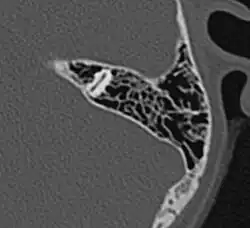

CT-Bild: Komplett pneumatisierte Felsenbeinpyramide von oben (schwarz = Luft). Gut sichtbar der obere Bogengang.

Die vom Mittelohr ausgehende Pneumatisation des Schläfenbeines ist mit dem fünften bis sechsten Lebensjahr weitgehend abgeschlossen. Ergebnis dieses Vorganges sind die pneumatischen Zellen, vor allem im Warzenfortsatz (Processus mastoideus). Es sind kleine, von Schleimhaut ausgekleidete Hohlräume, die durch unterschiedlich große Öffnungen miteinander und in der Gesamtheit mit dem Antrum mastoideum und damit mit dem Mittelohr in Verbindung stehen. Das Ausmaß der Pneumatisation des Schläfenbeines kann sehr unterschiedlich sein, es gibt Schläfenbeine mit fast komplett fehlender („gehemmter“) Pneumatisation, was meist als Folge häufiger Mittelohrentzündungen in der Kindheit anzusehen ist. Andererseits kann sich die Pneumatisation weit nach oben in die Schläfenbeinschuppe (Pars squamosa), nach vorne in den Jochbeinfortsatz (Processus zygomaticus) und in die Spitze der Felsenbeinpyramide ausdehnen. Es lassen sich im Warzenfortsatz typischerweise einzelne Zellgruppen oder Zellstraßen unterscheiden, die verschiedene Bezeichnungen tragen, wie Winkelzellen, Schwellenzellen, Terminalzellen usw. Dementsprechend werden bei ausgedehnter Pneumatisation Schuppenzellen (in der Schläfenbeinschuppe), Zygomaticuszellen (im Jochfortsatz), perilabyrinthäre Zellen (um das Labyrinth gelegen) und Pyramidenspitzenzellen unterschieden.